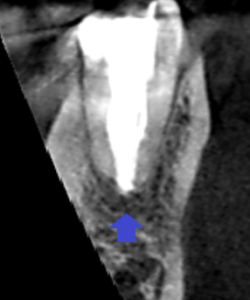

下顎大臼歯遠心根の冠状断のCT画像です。

赤い矢印の先に膿の影がみられます。根尖孔が大きく、

根の先まで根管充填で封鎖するのが難しいケースです。